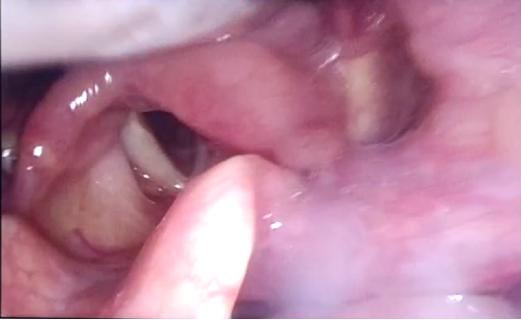

經(jīng)康復科吞咽康復系統(tǒng)治療后,程阿姨吞咽功能明顯改善,顏面口肌功能得到較大提高,舌各向抗阻,咽反射均較前好轉(zhuǎn)。近日,在給患者吞咽特調(diào)的綠染中稠流質(zhì)食物和綠染液體各3ml和5ml后,觀察到患者吞咽啟動可,會厭谷、梨狀竇無染色食物殘留,無滲漏,無誤吸,無嗆咳,即治療一療程后,吞咽功能明顯改善,在能經(jīng)口保證足夠營養(yǎng)攝入的情況下,建議可拔除鼻飼管,提高了程阿姨的生活質(zhì)量。

圖為吞食綠染液體后,喉內(nèi)鏡下顯示,會厭谷、梨狀竇無綠染色液體殘留,無滲漏,無誤吸。